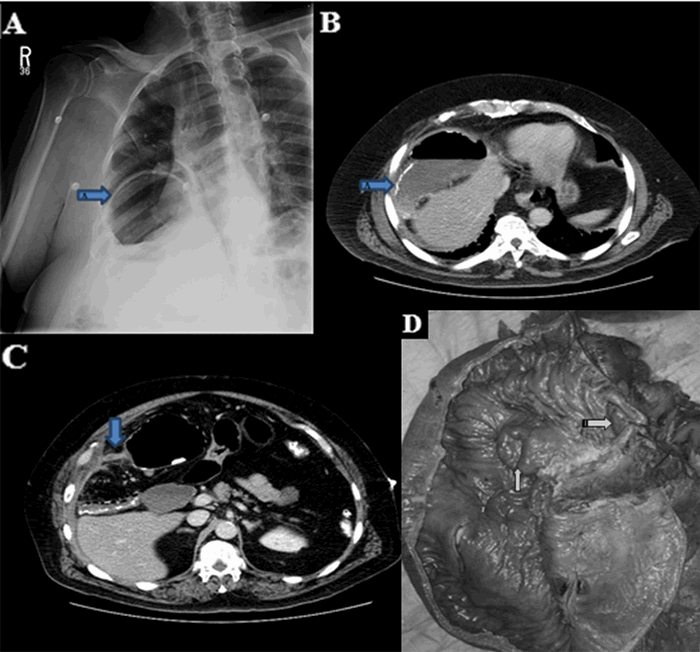

A 59-year-old female presented with sudden onset of right-sided abdominal and chest pain. She had prior similar episodes in the past; however, this pain was more intense and lasted longer, prompting her to seek medical attention. The patient had associated nausea but denied vomiting or change in bowel habits. Past medical history was significant for gastroesophageal reflux disease. Her vital signs were stable, and the abdomen was soft on exam without guarding. Upright chest X ray revealed air under the right diaphragm (Figure 2a). A CT scan demonstrated a large, right-sided Morgagni-type diaphragmatic hernia (Figure 2b). We performed an elective laparoscopic hernia repair with mesh that confirmed an anteromedial diaphragmatic hernia measuring 8 cm x 4 cm containing small bowel, colon, and omentum (Figure 2c and Figure 2d). The postoperative course was uneventful, and the patient was discharged home on postoperative day two.

Figure 2. Morgagni type diaphragmatic hernia. A) Plain film demonstrating air under the right diaphragm. B) CT scan demonstrating large right-sided Morgagni-type diaphragmatic hernia. C) Intraoperative picture of right-sided Morgagni-type diaphragmatic hernia. D) Morgagni-type diaphragmatic hernia after preperitoneal mesh repair.